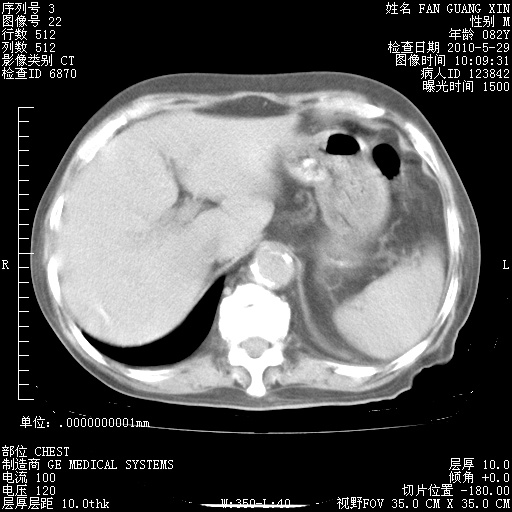

还需要哪些辅助检查?我们医院排除真菌感染没有任何检验方法,胸片好像能够排除肺部真菌感染。

补充:ENA化验全部阴性。免疫五项(IgG、IgA、IgM、C3、C4)只有C4略高。

CD3+ T细胞/淋巴细胞 46% (参考值50.00~84.00%)

CD3+CD4+ T细胞/淋巴细胞 21% (参考值27.00~51.00%)

CD3+CD8+ T细胞/淋巴细胞 25% (参考值15.00~44.00%)

CD3+CD4+ T细胞/CD3+CD8+ T细胞 0.84 (参考值0.71~2.78)

T细胞亚群是治疗5天采血。